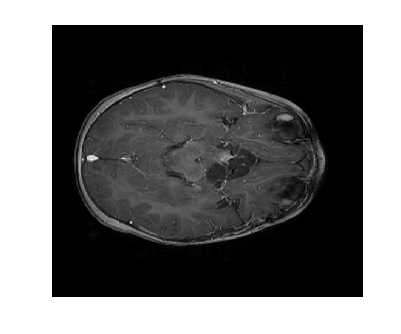

Figure 12: (a) is the ground truth of the follow-up image, (b) is the reference image (with scaling parameter c=2𝑐2c=2), (c) and (d) are reconstructions with η𝜂\eta=0.06 over 3 sampling iterations using LACS-MRI.

Figure 12 shows the effect of a 2-fold scale difference on LACS-MRI image reconstructions. There are extensive streaking artifacts and significant detail is lost compared to the ground truth and the reconstruction using the modified method. Clearly, the Grayscale Compensation for Reference Based MRI Algorithm (GSC) can reduce these artifacts and help improve the visibility of structure.